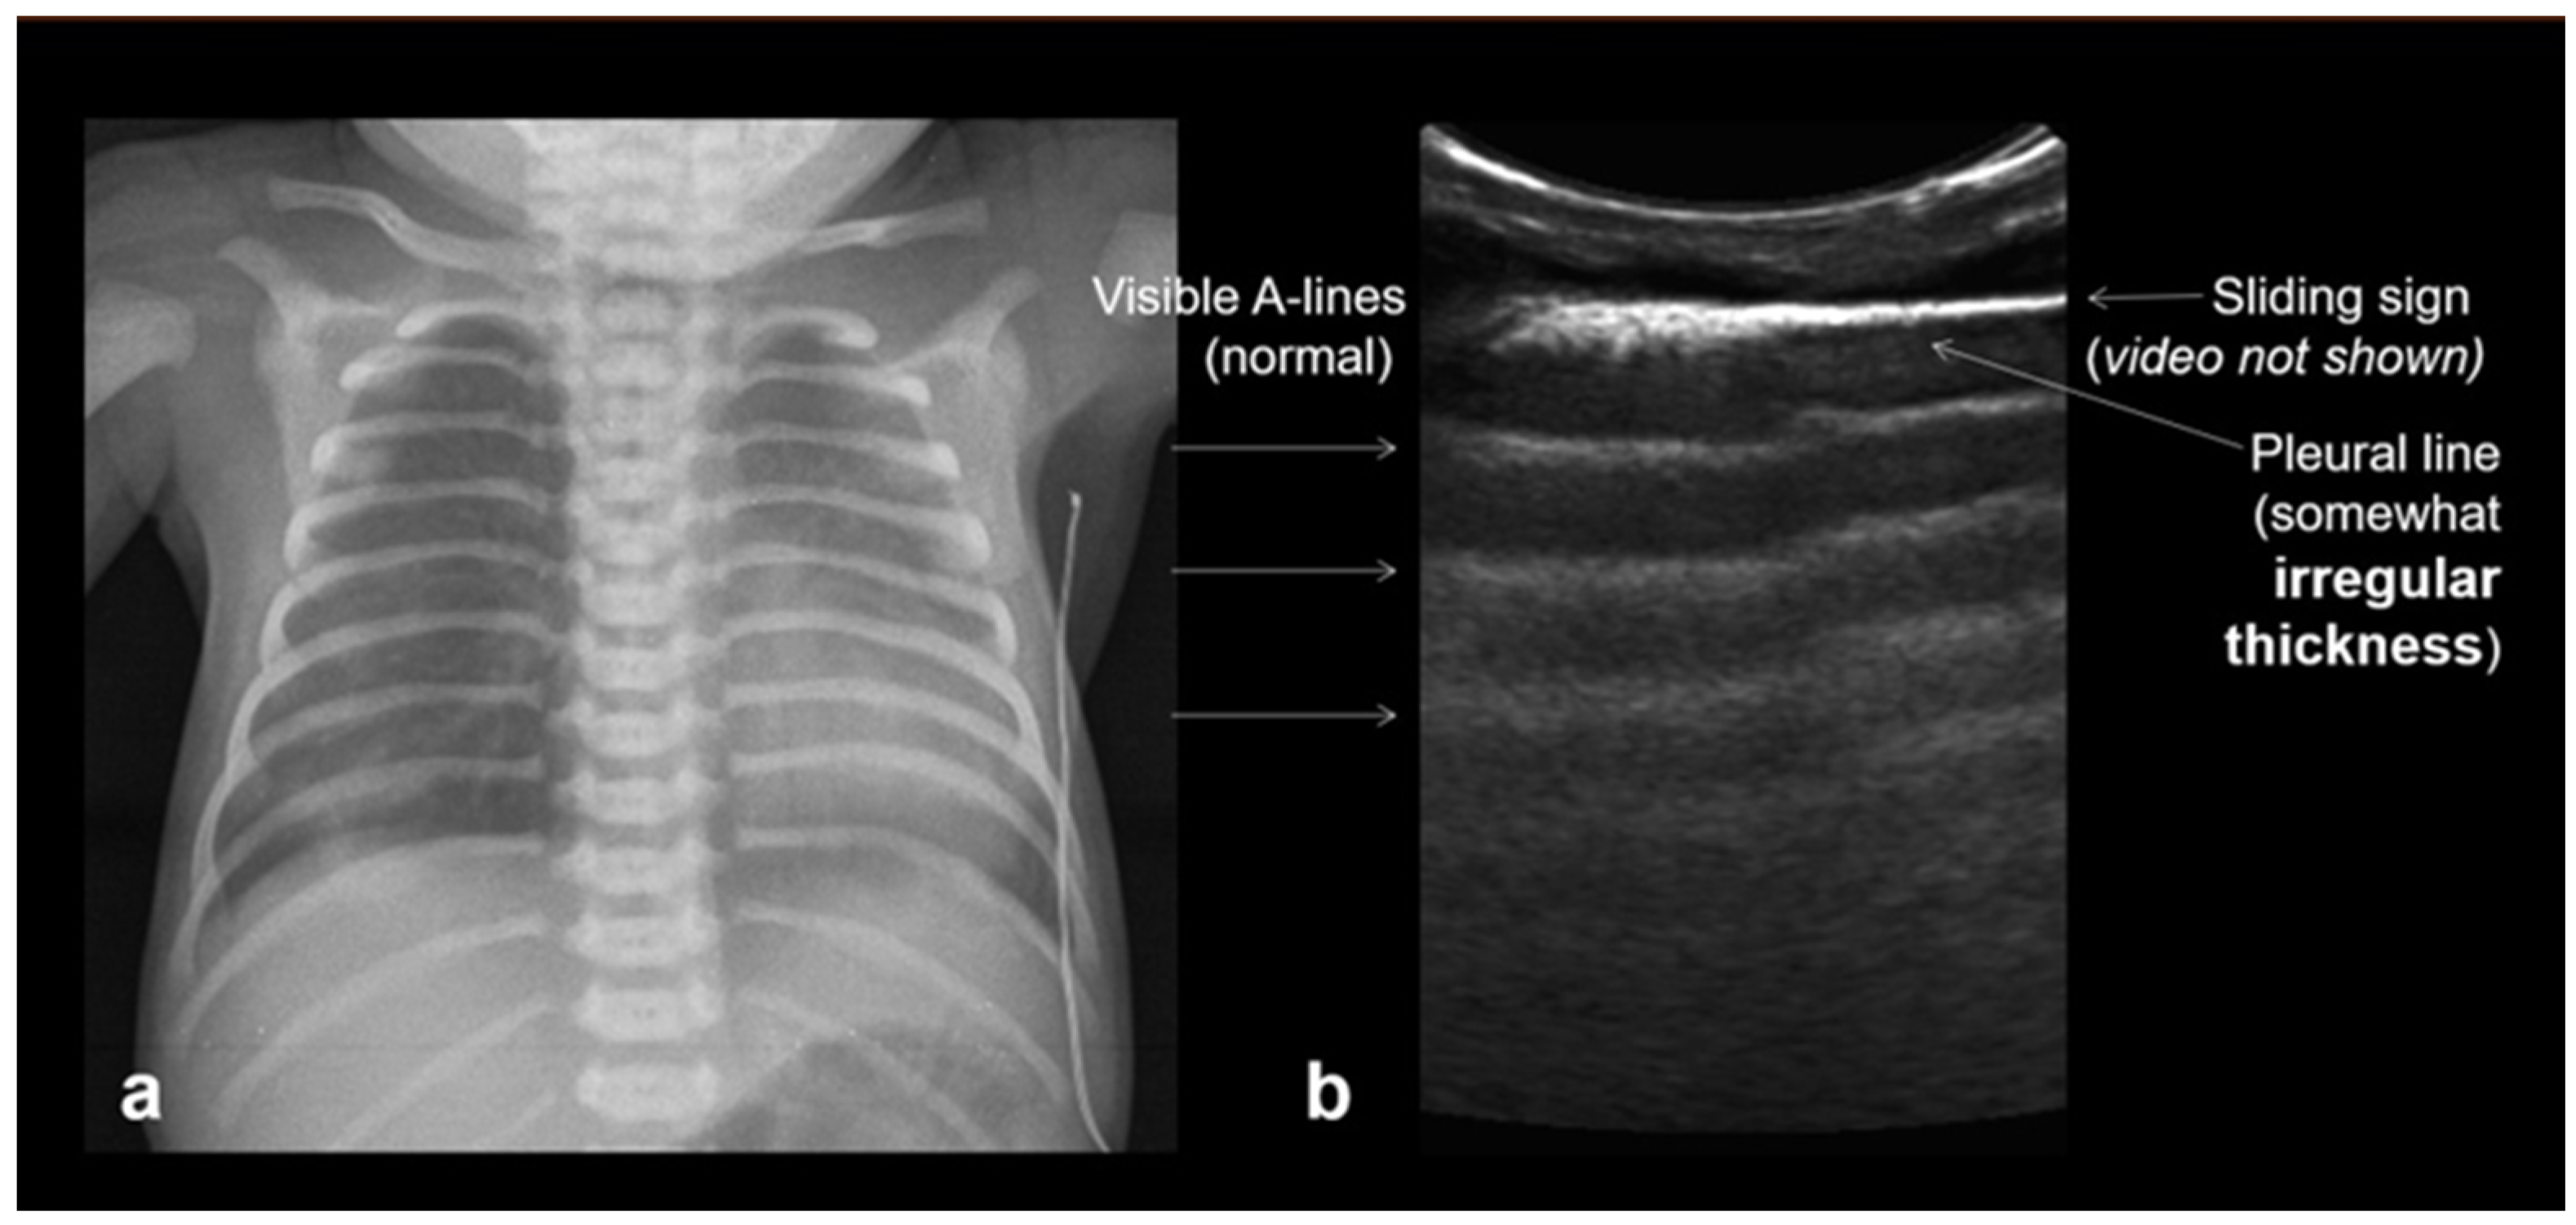

3.2.4. Respiratory Distress Syndrome (RDS)

In RDS, lung ultrasound findings include consolidation or bilateral “white lung”, aero bronchograms, pleural line abnormalities, and the absence of A-lines (Figure 12, Figure 13, Figure 14 and Figure 15) [30,35,40,41].

Figure 12.

A frequent and characteristic imaging finding in RDS is the presence of B-Lines, bilaterally and throughout the lung parenchyma, in this case bilateral B-lines with no normal parenchyma (a) (absence of A-lines). Also, note the abnormal thickening ((a,b) arrows) of the pleural line (b). The overall sense is that of white lung.

Figure 13.

Normal to mild RDS: by chest X-ray (a); by LUS (b).

Figure 14.

Severe RDS shown on chest X-ray (a); LUS (b). The ability of the LUS to characterize the severity of the RDS is debatable.

RDS is a common cause of neonatal respiratory failure, particularly in preterm infants, resulting from surfactant deficiency and alveolar collapse. LUS has become a valuable diagnostic tool for RDS, offering real-time visualization of lung pathology at the bedside [38,42,43,44,45]. A hallmark sonographic feature of RDS is the presence of dense, confluent B-lines throughout the lung fields, producing a “white lung” appearance due to the loss of normal aeration. Notably, the whole lung is typically involved, with a diffuse, bilateral distribution that distinguishes RDS from more localized pulmonary conditions [37,46,47]. Additionally, interspersed consolidations may be present, including hypoechoic and subpleural areas of alveolar collapse, reflecting regions of complete de-aeration. These consolidations often lack air bronchograms and are associated with irregular or thickened pleural lines. The combination of diffuse B-line patterns, global lung involvement, and patchy consolidations provides a highly suggestive ultrasound profile of RDS and facilitates early diagnosis. In addition, for RDS, LUS may be used for severity assessment and the monitoring of treatment response in the neonatal intensive care setting [16,20,27,29]. The ability of the LUS to characterize the severity of the RDS is debatable (Figure 14 and Figure 16) [48].